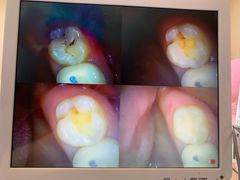

• 新达口腔(华东理工大学店)

• -新达口腔(华东理工大学店)

秋秋Doria_2656 | 20-07-02

食一场人间烟火 | 20-07-01